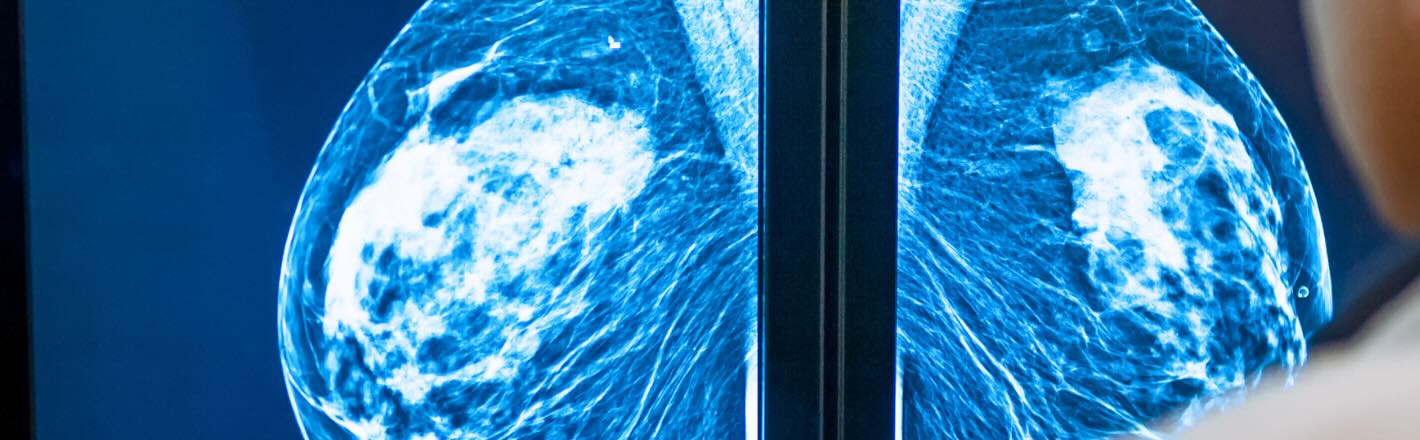

As DBT, CEM, and advanced breast imaging technologies become standard in mammography, radiation safety programs must evolve with them. This article explains how modern modalities influence scatter conditions, workflow proximity, dose trends, and what imaging leaders should prioritize to protect staff and strengthen compliance.

In my years overseeing imaging departments, one thing became increasingly clear: technology changes faster than many safety programs can keep up. Mammography is no exception. Digital breast tomosynthesis (DBT) has become the standard in many facilities. At the same time, contrast-enhanced mammography (CEM) is expanding rapidly as a lower-cost, highly accessible alternative to MRI. Even biopsy systems now rely on multi-step imaging workflows that look very different from traditional 2D mammography.

These technologies deliver enormous clinical value, but they also reshape the exposure landscape in ways that hospital imaging directors, RSOs, physicists, and technologists must account for. Modern modalities alter scatter patterns, increase throughput, extend room time, and create more exposure opportunities throughout the day.